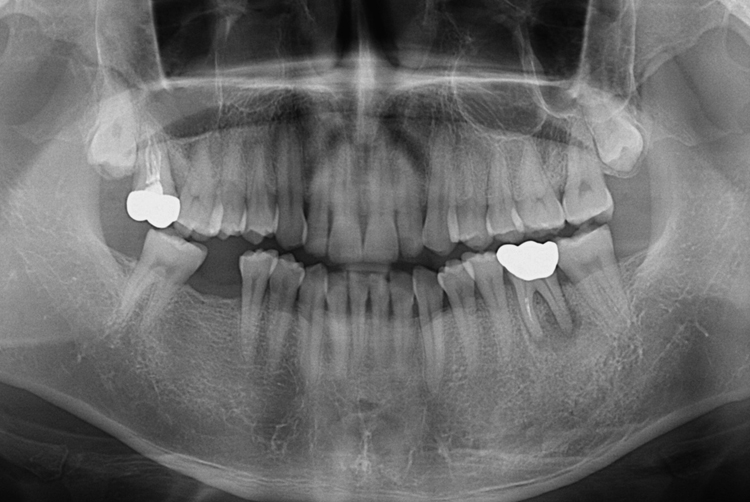

치료전 : 2019-03-19

2011.9.23.jpg